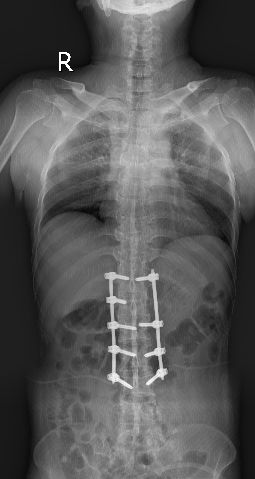

全脊柱正侧位显示骶髂关节间隙消失

脊柱竹节样融合改变

术后复查见腰1、腰2椎体高度恢复,螺钉位置满意